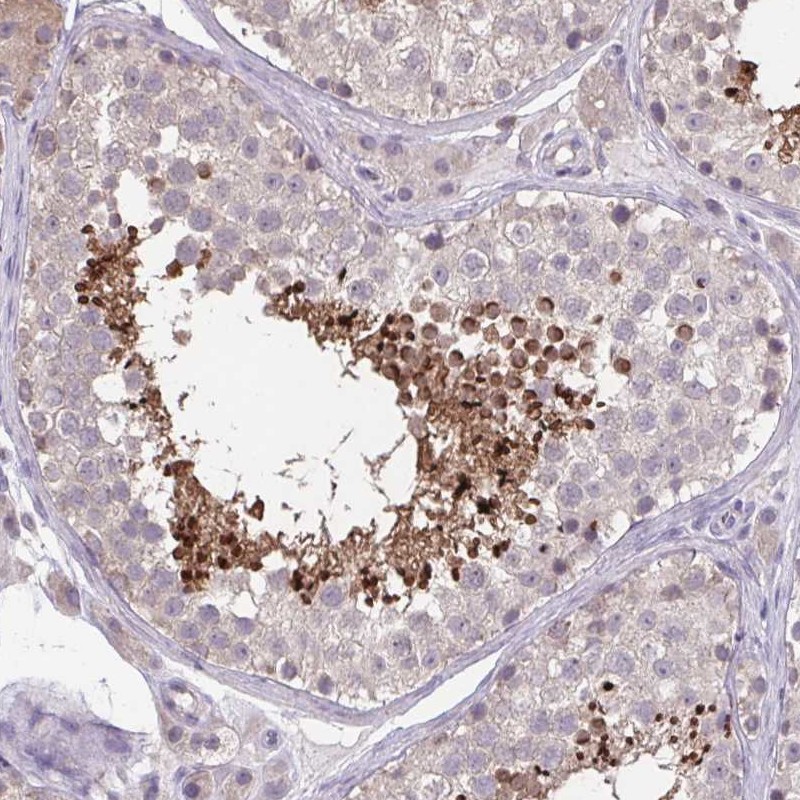

Immunohistochemistry analysis in human testis and endometrium tissues using Anti-ACTRT2 antibody. Corresponding ACTRT2 RNA-seq data are presented for the same tissues.